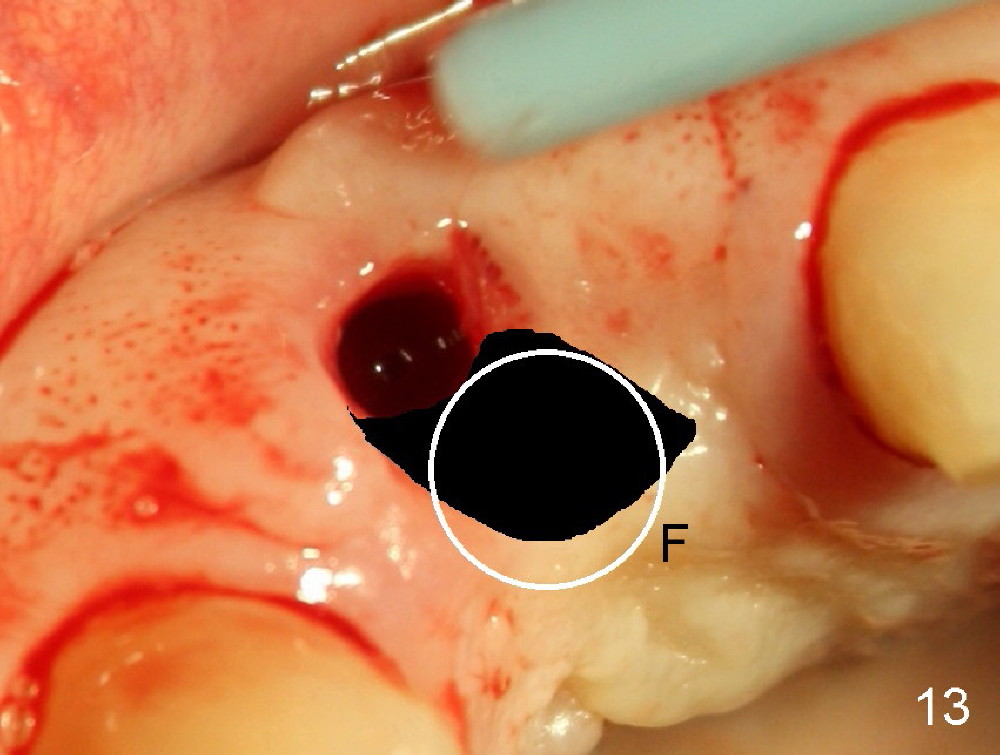

Malpositioned implant in the anterior region is cosmetically unacceptable. Immediate provisional allows us to note the issue immediately. The crown looks too long. Secondly, the provisional is easily dislodged, since the buccal aspect of the angled abutment is over trimmed (Fig.1). The implant (3.8x14 mm), which has been placed 3.5 months, is unexpectedly easily removed by reverse torque (Fig.2). The buccal wall is intact, whereas there seems to be enough bone lingually to place an implant. A small incision is made (Fig.11) so that the gingival tissue can be transferred buccally (Fig.12) and the immediate implant is to be placed palatally (Fig.13 white circle). There is no difficulty forming osteotomy in the palatal wall, followed by inserting 4.5x20 mm tap at the depth of 17 mm (Fig.3,5). But the tap is not palatal enough (Fig.4). By removing more palatal bone, the 4.5x17 implant (Fig.6) appears to be placed palatally enough for restoration (Fig.7; A: abutment; *: buccal gap). The biggest problem is that the palatal flap (Fig.7 arrowheads) cannot be pushed buccally; instead remains palatally. This leads to buccal tissue deficiency (Fig.8). Connective tissue graft is offered, but declined. The patient insists that she has low smile line. Following immediate provisional, mixture of allograft and synthetic graft is placed in the buccal gap (Fig.9). The overbuilt graft is held in place by perio dressing.